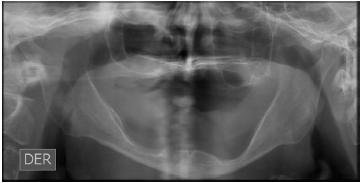

Paciente portadora de prótesis removible desde hace más de 30 años que acude porque desea una rehabilitación fija. En la anamnesis relata que en 2 ocasiones ha perdido implantes en el sector inferior. Al examen clínico y de imagen se observa reabsorción ósea severa de ambos maxilares y neumatización extrema (fig. 1).